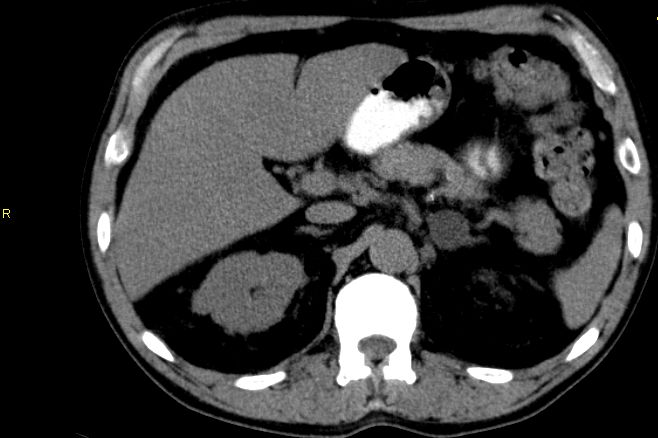

Epidemiologie 1/3 Phaeochromozytom, 1/4 hormoninaktiv, 1/5 Conn, 17% Cushing

Adenom

Tumor